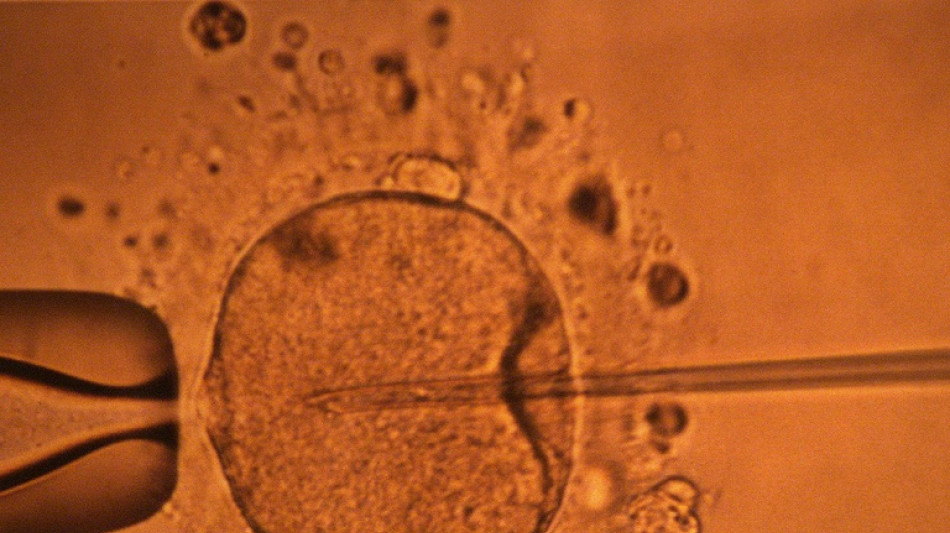

Un estudio apoya hipótesis de disminución mundial de concentración de espermatozoides / Foto: © AFP/Archivos

La concentración de espermatozoides, uno de los factores de la fertilidad masculina, disminuyó significativamente en todo el planeta en las últimas décadas, según un estudio publicado el martes.